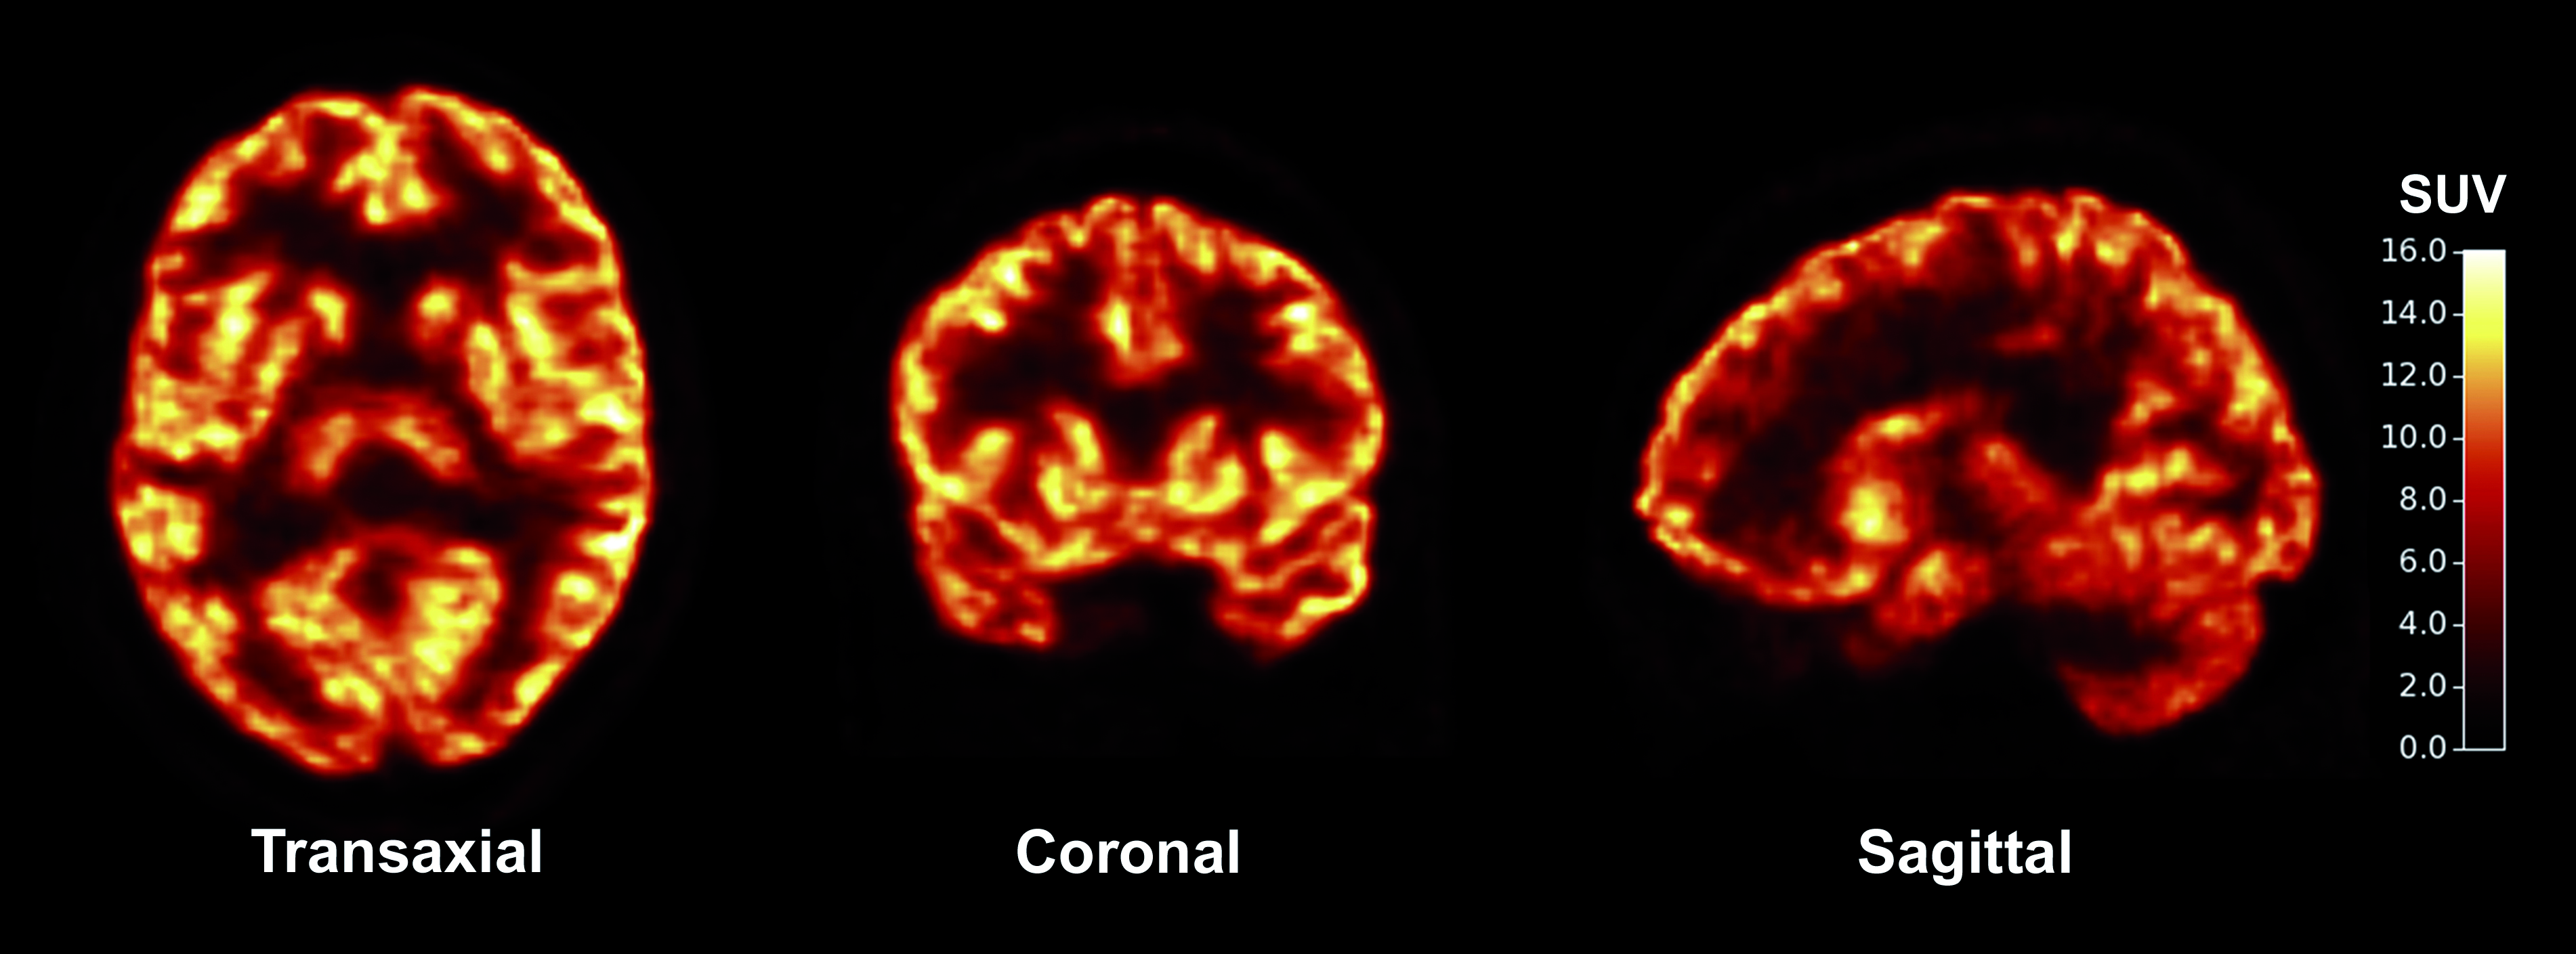

To find a non-invasive approach, the Yale-led team developed a radioactive compound, called a tracer, that is injected into the body and binds with a particular protein that is found in the brain's synapses. The idea: During a PET scan, those synapses appear lit up against dark, synapse-free areas of the brain.

The research team then mapped the density of synapses in the brains of 10 healthy volunteers and three patients with a form of epilepsy. Compared to the healthy brains, the technique revealed lost synapses in the epilepsy-affected regions of those patients' brains, the researchers reported Wednesday in the journal Science Translational Medicine.